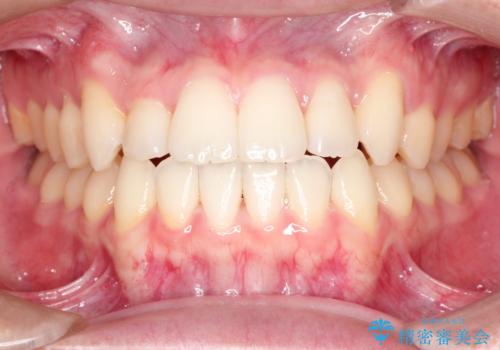

前歯のデコボコ インビザラインによる目立たない矯正

- 前歯のデコボコを主訴に来院された患者様です。

目立たないそうちをご希望されたので、インビザラインにて治療することとしました。

歯と歯の間をわずかに削ってスペースをつくり、デコボコを改善しました。